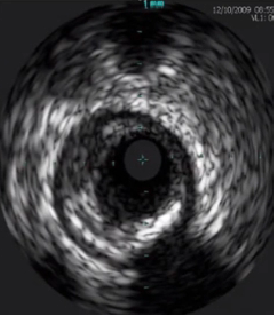

特殊斑块影像

超声衰减斑块

(破裂后无复流率高)

特殊钙化影像

钙化结节(Angio充盈缺损)